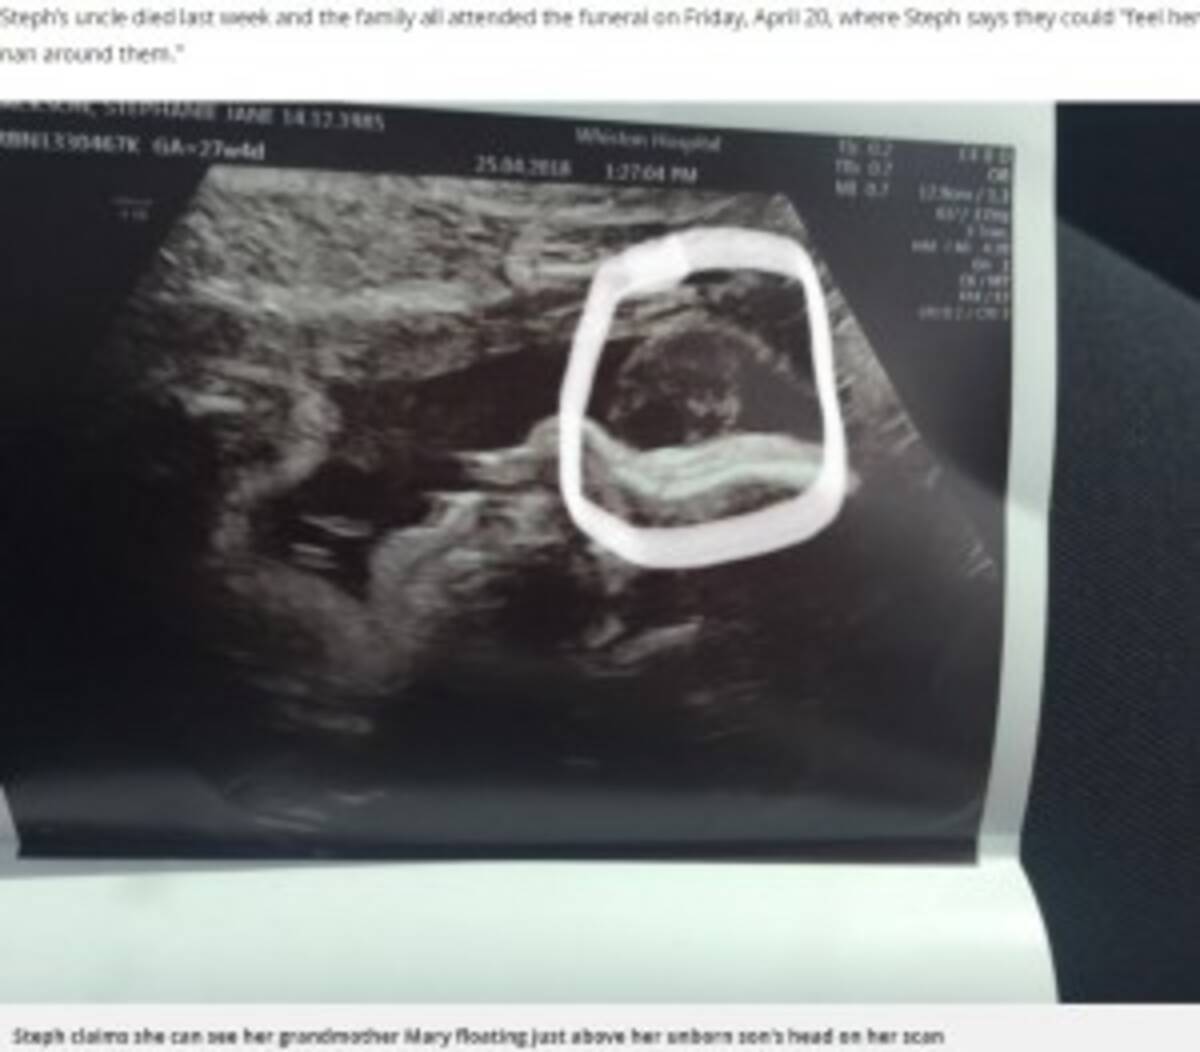

おばあちゃんがここに 胎児のエコー写真に亡き祖母の顔が 英 18年5月3日 エキサイトニュース